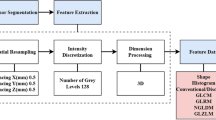

A total of 126 patients diagnosed with pituitary adenoma (N = 63) or craniopharyngioma (N = 63) were enrolled. Qualitative magnetic resonance (MR) image features and texture features of tumors were extracted from preoperative MRI and evaluated using chi-square test or Mann–Whitney U test. Binary logistic regression analyses were performed to assess their abilities as independent diagnostic predictors, and ROC analyses were conducted to evaluate the diagnostic value of significant features. Mann–Whitney U test and ROC analyses were performed to explore the relationship between MR image features and texture features.

Five MR image features were suggested to be significantly different between pituitary adenoma and craniopharyngioma. Three texture features from contrast-enhanced T1WI (HISTO-Skewness, GLCM-Contrast and GLCM-Energy), two texture features from T2WI (HISTO-Skewness and GLCM-Contrast) showed significant differences between two types of tumors. Logistic regression analyses suggested GLCM-Energy from contrast-enhanced T1WI, HISTO-Skewness and GLCM-Contrast from T2WI could be taken as independent predictors. Moreover, HISTO-Skewness and GLCM-Contrast from T2WI were found to be significantly related to cystic change.

Nioche C, Orlhac F, Boughdad S, Reuzé S, Goya-Outi J, Robert C, et al. Lifex a freeware for radiomic feature calculation in multimodality imaging to accelerate advances in the characterization of tumor heterogeneity. Cancer Res. 2018;78(16):4786–9. https://doi.org/10.1158/0008-5472.can-18-0125.